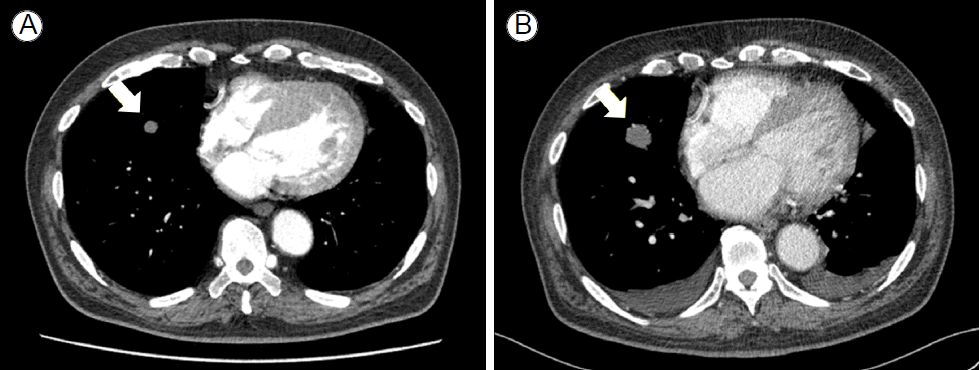

방사선 소견: 응급실에서 촬영한 단순 흉부방사선 사진은 정상이었으나, 흉부 전산화단층촬영에서는 양폐야에 간유리 음영을 동반한 여러 개의 다양한 크기의 결절들이 관찰되어(Fig. 1) 전산화단층촬영 유도하에 경피적 폐침생검을 시행하였다.

경과: 환자의 만성 출혈에 대한 고식적 수술과 전신 항암화학치료를 계획하였으나, 환자는 허혈성 심질환 등의 다른 건강상의 이유로 치료방법을 결정하지 못하여 자의로 퇴원하였다. 그러나 1개월 후에 발열, 기침, 호흡곤란이 발생하여 다시 본원 응급실로 내원하였고, 추적 흉부 전산화단층촬영에서 폐 결절들의 크기 및 개수가 증가하였으며, 부폐렴성 흉수도 관찰되어 혈관육종의 경과가 급격히 진행함을 알 수 있었다(Fig. 1).